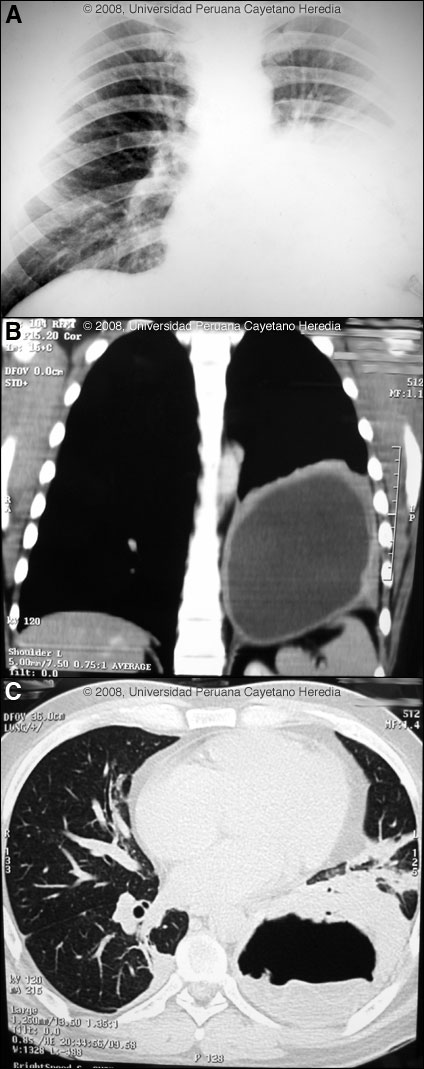

![]() Discussion: A Western Blot taken before the acute rupture was strongly positive for E. granulosus. The expectoration of large amounts of salty fluid is highly characteristic of this catastrophic event. The 2nd CT scan showed no pleural fluid indicating erosion and rupture of the cyst only into the bronchus. The elevated peripheral WBC is likely indicative of some bacterial superinfection post-rupture. Human hydatid disease secondary to Echinococcus granulosus is caused by the larval form of this dog tapeworm. Humans ingest the tapeworm eggs in environments contaminated by canine feces and become accidental intermediate hosts. Sheep are the normal intermediate hosts. Larval cysts expand slowly over years or decades becoming symptomatic as they impinge on other structures by virtue of their size. Spontaneous cyst rupture as occurred here happens in the minority of cases but is not rare. The cysts contain hundreds of viable scoleces capable of becoming adult tapeworms upon ingestion by a definitive host such as the dog. The internal germinal membrane lining the cyst produces new scoleces on an ongoing basis. Each scolex is capable of becoming a new daughter cyst either within the original cyst or elsewhere should the original cyst rupture or be ruptured. An example of seeding of the pleural cavity is seen in a previous case of the week (Gorgas Case 2005-10). Hydatid disease is common in sheep-raising areas worldwide. Most primary infections involve a single cyst. 65% of solitary cysts are found in liver, 25% in lung and the rest in a wide variety of other organs including kidney, spleen, heart, bone and brain. In patients with a pulmonary cyst, approximately 15% will also have a hepatic cyst. Serology is usually positive with hepatic cysts but sensitivity drops below 50% with solitary pulmonary cysts even when the cyst is large. With the large burden of disease in this patient’s lung a positive serology would be expected. Praziquantel is the most potent scolicidal drug and is the drug of choice for all adult tapeworms. However, praziquantel cannot penetrate the hydatid cyst wall so is only useful as an acute therapy when a cyst ruptures (spontaneously or due to surgical mishap) and scoleces are lying free before encysting again. Albendazole is the therapy of choice for intact cysts that are not operable, such as when there are multiple or diseminated cysts. A trial of Albendazole may also be considered for solitary cysts that are less than about 10 cm. Response is generally slow and only complete in a minority of cases. Surgical resection is the therapy of choice for large intact solitary cysts and certainly in a case like this with an acute rupture and a broncial-cyst fistula. At thoracotomy, the cyst was found to be intact on all surfaces within the lung parenchyma and was flaccid with little remaining fluid indicating that fortunately no fluid (which would contain protoscoleces) [Images D, E] had escaped into the pleural space. Unfortunately, the outer membranes were highly adherent to the lung parenchyma precluding shelling out and removal of the cyst alone and necessitating a left lower lobectomy. Image F shows the inner or germinal membrane that lines the cyst and that is responsible for the ongoing generation of new protoscoleces as the cyst grows in size. Perioperative Albendazole in case of cyst rupture during the procedure is frequently utilized for hepatic cysts even though scolididal agents are always injected into the cyst intraoperatively before any resection is attempted. In the case of pulmonary cysts most surgeons feel that cyst softening that may occur with albendazole makes the operative procedure more complicated and increases the risk of rupture at the time of resection.